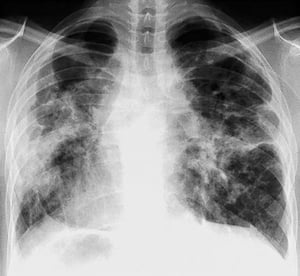

Sarcoidosi (stadio I)

Adenopatia ilare bilaterale nella sarcoidosi di stadio I.

By permission of the publisher. Da Tanoue L, Elias J. In Bone's Atlas of Pulmonary and Critical Care Medicine. Edited by J Crapo. Philadelphia, Current Medicine, 2005.